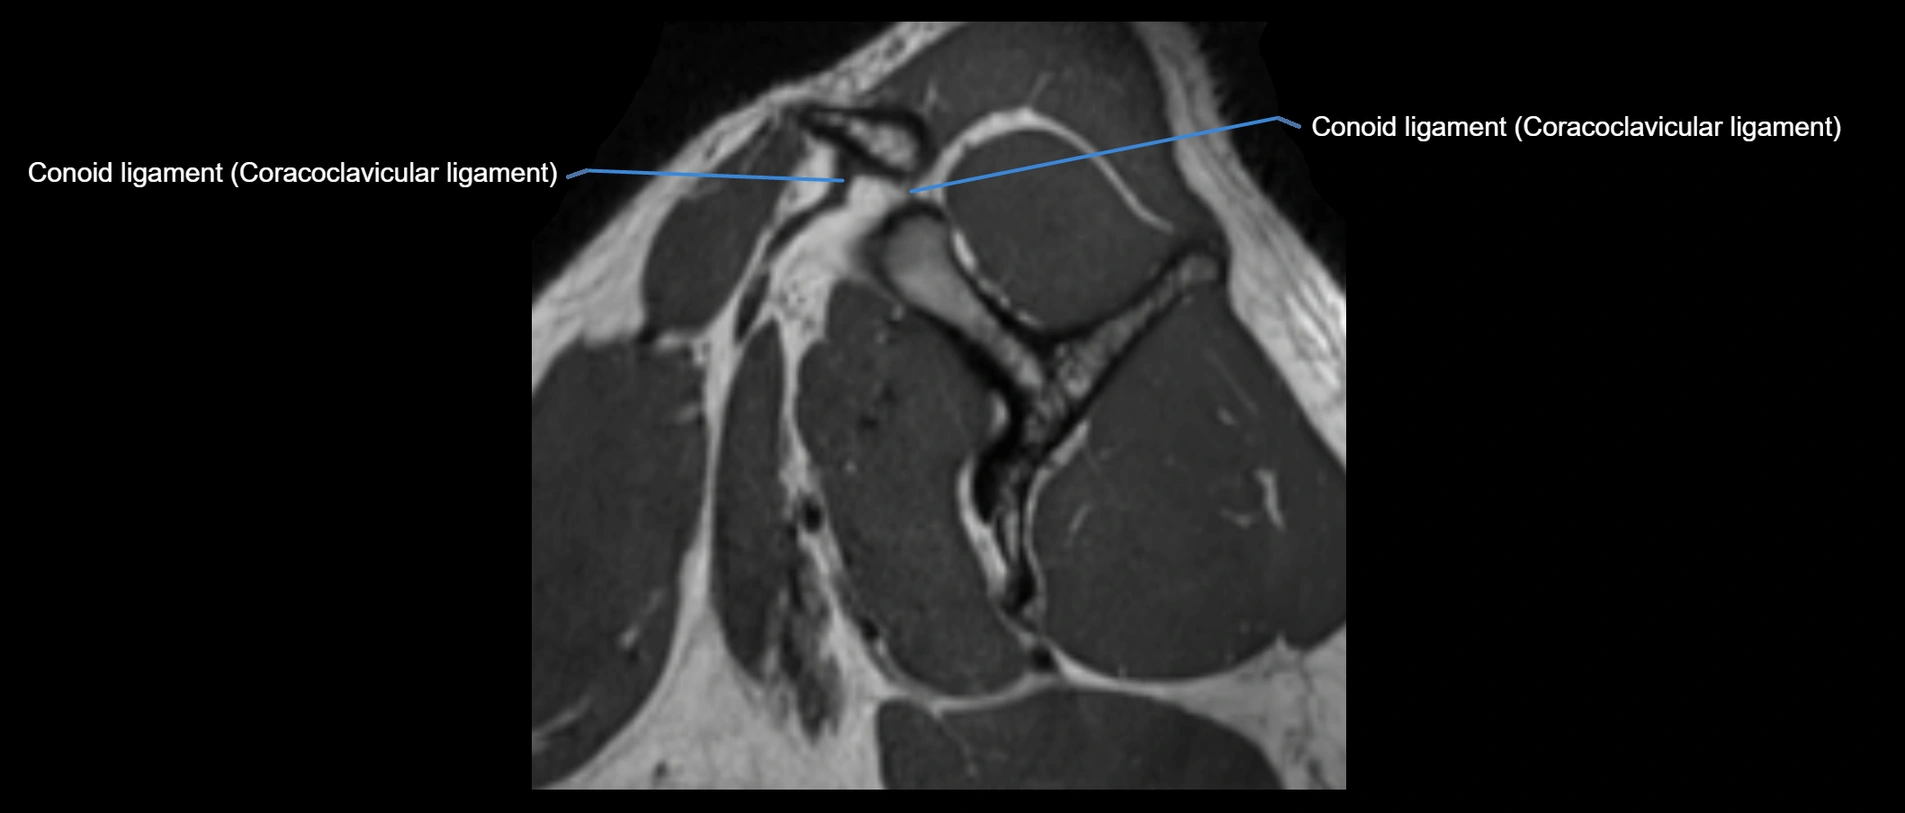

MRI images

image